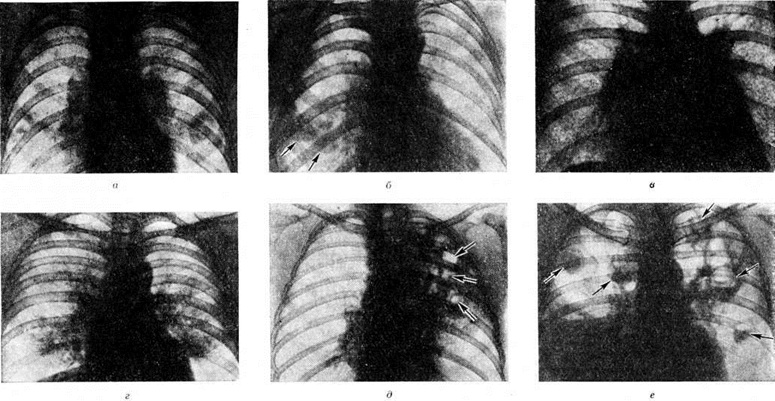

По локализации и объёму поражения лёгких различают следующие формы Пневмония: долевую, или лобарную, Пневмония— при поражении целой доли лёгкого (в этом случае применяют термин «крупозная пневмония»); очаговую Пневмония— при поражении части сегмента, целого сегмента или нескольких сегментов лёгких. В связи с тем, что при очаговой Пневмония обычно поражаются и бронхи, в качестве синонима используется термин «бронхопневмония». Воспалительный процесс при очаговой Пневмония чаще локализуется в нижних долях лёгкого, особенно справа, иногда бывает двусторонним. В случае слияния ряда очагов создаётся впечатление о поражении целой доли (цветной рисунок 1), что обозначается термином псевдолобарная Пневмония (например, при Пневмония, вызванной палочкой Фридлендера). При локализации патологический изменений в строме лёгкого Пневмония называют интерстициальной или межуточной; такие изменения, однако, редко бывают воспалительными в полном смысле слова, как правило, это лимфогистиоцитарно-плазмоцитарные, чаще периваскулярные и перибронхиальные инфильтраты, являющиеся местным проявлением иммунологический реакций. При поражении в основном респираторных отделов лёгких патологоанатомически выделяют альвеолиты — форму Пневмония, характеризующуюся выраженными изменениями альвеолоцитов.

Рис. 1. Макропрепарат лёгкого при пневмонии, вызванной палочкой Фридлендера, стрелками указаны сливающиеся очаги в верхней доле лёгкого (псевдолобарная пневмония).

Рис. 2. Макропрепарат лёгкого при стрептококковой очаговой пневмонии: сливные очаги в нижней доле лёгкого (указаны стрелками).

Рис. 3. Макропрепарат лёгкого при гипостатической (застойной)пневмонии: обширные участки пневмонии (указано стрелкой) в задних нижних сегментах лёгкого.

Рис. 3—5. Микропрепараты лёгких при некоторых формах бронхопневмонии.

Рис. 3. Серозно-гнойная пневмония: альвеолы заполнены серозной жидкостью с примесью полиморфно-ядерных лейкоцитов (указаны стрелками); окраска по Грам-Вейгерту; × 36.

Рис. 4. Гнойный бронхит: в просвете бронха гнойно-фибринозная пробка (указана стрелкой); окраска гематоксилинэозином; х 80.

Рис. 5. Плевропневмония: отложения фибрина (7) на плевре, в альвеолах серозно-гнойный экссудат (2), окраска гематоксилин-эозином; × 36.